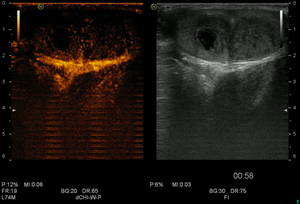

Ультразвуковое исследование мошонки

- Исследование в В-режиме линейным датчиком

- Исследование в режиме ЦДК и ЭДК